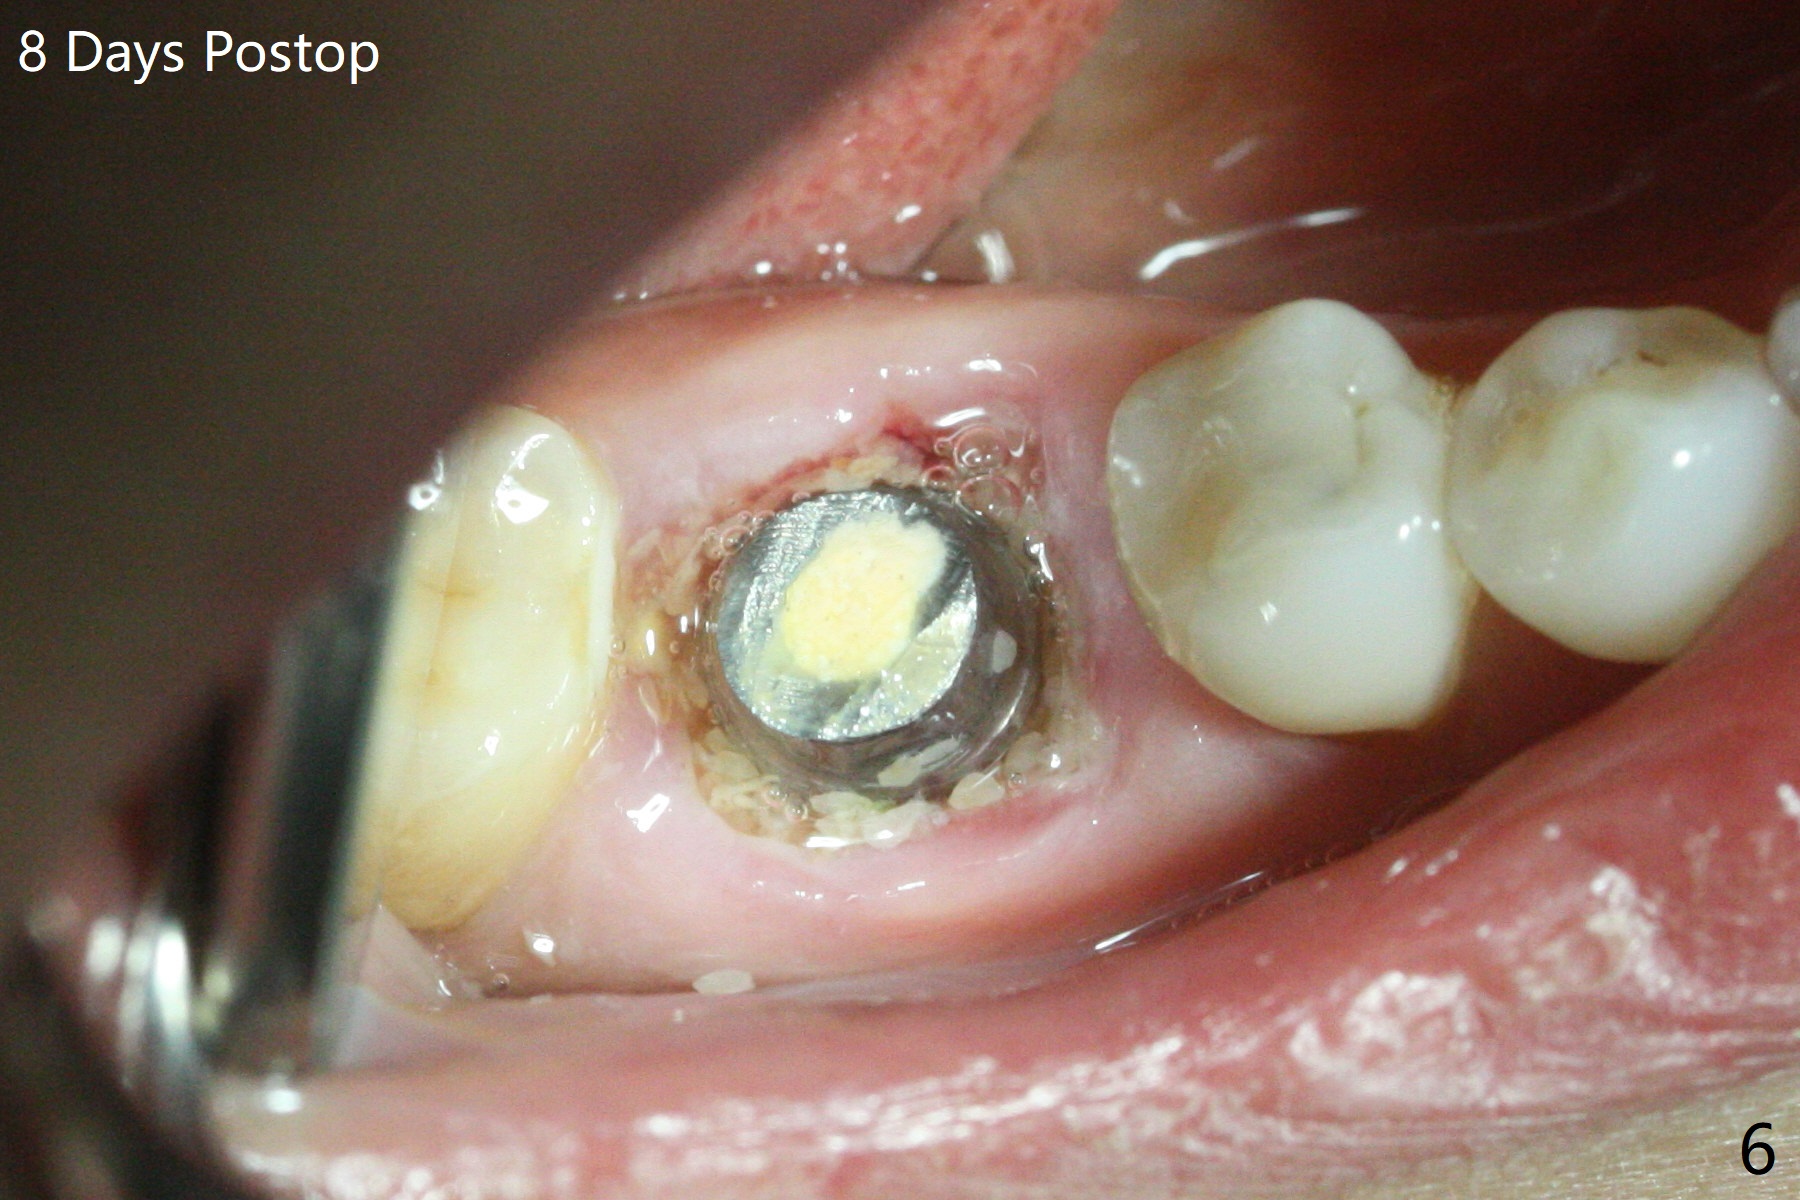

牙冠断裂,好像容易保留牙根,其实还挺多工作。使用12毫米平磨钻头后,中隔中央形成凹陷,不过使用2.2x7.3毫米钻头后,钻洞开始偏移远中(图一)。完成3.5x11.5毫米钻洞,4x10毫米报废植体扭力很高(图二)。为了植入5x11毫米植体(扭力35Ncm),必须使用4.5x11.5毫米钻头(图三)。虽然根尖骨质不多,稳定性部分来自残余颊侧,舌侧中隔。即刻放置的基台远中舌侧必须大量磨去(图四:^)才有足够空间做临时牙冠,说明牙冠会折裂病人咬合力大。保留牙根工作量大,仍有偏差(与图五(设计)相比),仿佛好处不大,以后少做。由于临时牙冠舌侧做的大些,术后八天取出修正,伤口愈合正常(图六)。术后一个月一部分骨粉好像被转化为牙龈(图七)。术后3.5月病人抱怨咀嚼疼痛,植体松动,放置愈合基台。一个月后植体仍松动,疼痛(图八)。术后6.5月,植体不再松动,放置修复基台(图九),取模。